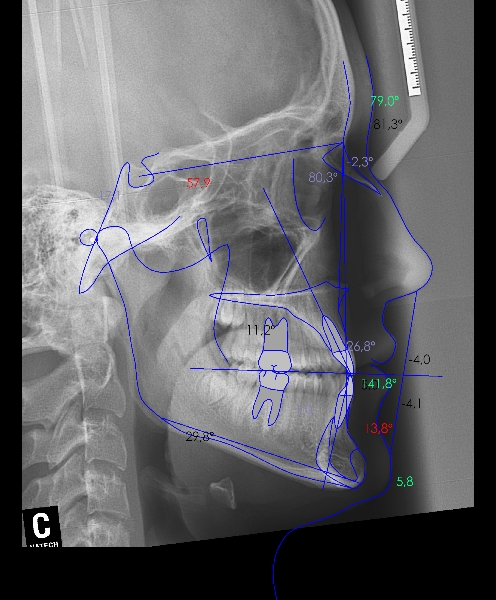

Chica de 17 años tratada en 1 año con stripping en los dientes inferiores

El stripping consiste en la reducción interproximal del esmalte entre los dientes posteriores y anteriores, así obtenemos espacio para alinear los dientes apiñados.